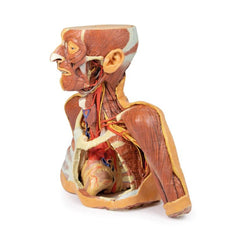

This 3D model is a midsagittal hemisection through a whole brain, preserving the right side anatomy and deep brain

structures and spaces visible in the midline. In lateral view, the right cerebral and cerebellar hemispheres are

covered in the arachnoid mater. In the midline view, the brain regions from the cerebrum to the medulla oblongata

are preserved. Centrally, the third ventricle is opened, with an intact septum pellucidum superiorly positioned and

obscuring the lateral ventricles within the cerebral hemisphere. On the inferior margin of the third ventricle both

the right mamillary body and right optic tract can be observed, whereas posteriorly the cerebral aqueduct can be

observed extending across the midbrain between the tectum and tegmentum towards the fourth ventricle (between the

cerebellum and pons). The cerebellum is separated from the occipital lobe by a preserved portion of the tentorium

cerebelli, and in cross-section the cerebellar cortex helps form the prominent arbor vitae.

A series of arterial

branches have been false coloured to contrast their course across the preserved brain structures. In the midsagittal

view the anterior cerebral artery courses from around the corpus callosum to supply the cingulate gyrus and other

midline cortical regions. The base of the middle cerebral artery can be seen passing deep between the temporal and

frontal lobes, with the posterior communicating artery connecting it to a small remnant of the posterior cerebral

artery. Adjacent to the posterior cerebral is the superior cerebellar artery, extending laterally to pass between

the temporal lobe and the cerebellum before passing deep into the transverse fissure.